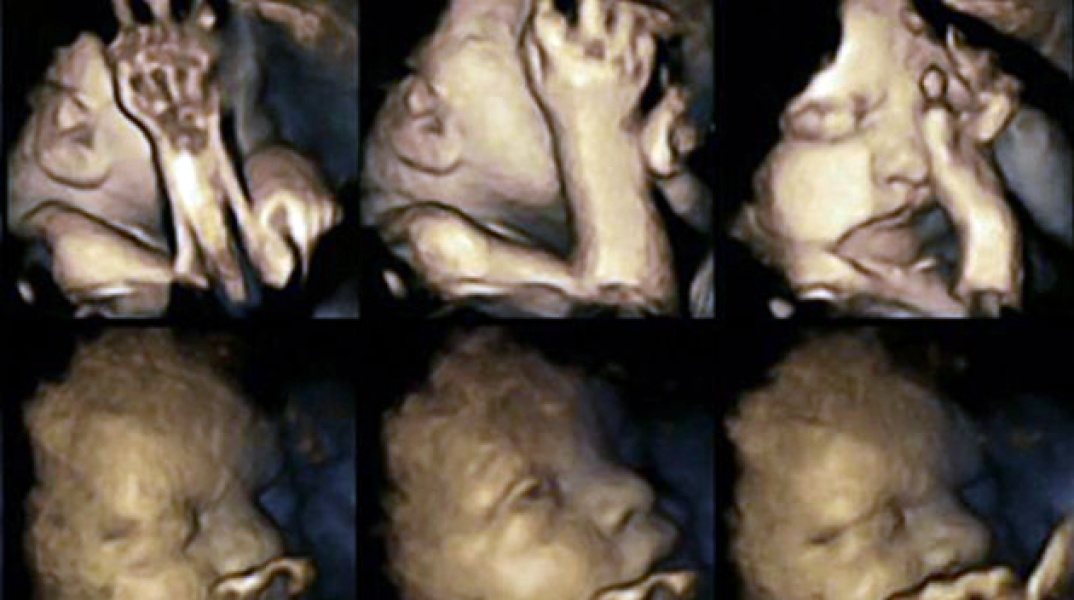

Οι επιστήμονες ελπίζουν ότι αυτές οι εικόνες θα πείσουν πολλές μητέρες

Επιστήμονες στη Βρετανία είναι σε θέση να πιστεύουν ότι θα μπορούν πια όχι μόνο με τα λόγια, αλλά με αδιάψευστες εικόνες να δείξουν στις γυναίκες που καπνίζουν συστηματικά κατά τη διάρκεια της κύησης πώς αντιδρά το έμβρυο στις ουσίες του τσιγάρου μέσα από τη μήτρα. Επικεφαλής της έρευνας είναι η δρ. Νάγια Ρέισλαντ από το Πανεπιστήμιο του Ντάραμ, η οποία με υπερηχογράφους 4-D κατάφερε να απεικονίσει τις αντιδράσεις των εμβρύων στις ουσίες του τσιγάρου. Η δρ. Νάγια Ρέισλαντ διαπίστωσε ότι τα έμβρυα των γυναικών που κάπνιζαν περίπου 14 τσιγάρα την ημέρα, παρουσίαζαν έντονη κινητικότητα στο στόμα, ενώ άγγιζαν συνεχώς την περιοχή του στόματος και της μύτης με τα χέρια τους. Αντιθέτως, όσα δεν εκτίθονταν στις ουσίες του τσιγάρου, παρουσίασαν φυσιολογική συμπεριφορά, χωρίς αυξημένη κινητικότητα στις προαναφερθείσες περιοχές. Η γιατρός παρακολούθησε 20 μητέρες εκ των οποίων οι τέσσερις κάπνιζαν κατά μέσο όρο 14 τσιγάρα την ημέρα.

Η πιλοτική μελέτη ελπίζει να διευρύνει το δείγμα της έρευνας σε περισσότερες γυναίκες ώστε να διαπιστώσει αν πράγματι το κάπνισμα κατά τη διάρκεια της εγκυμοσύνης επηρεάζει σημαντικά την ανάπτυξη του νευρικού συστήματος των εμβρύων. Η δρ. Νάγια Ρέισλαντ ευχαρίστησε όλες τις γυναίκες που συμμετείχαν εθελοντικά στην έρευνα και κυρίως τις καπνίστριες. Διαβεβαίωσε, επίσης, ότι τα μωρά όλων αυτών των γυναικών γεννήθηκαν χωρίς κανένα πρόβλημα υγείας.